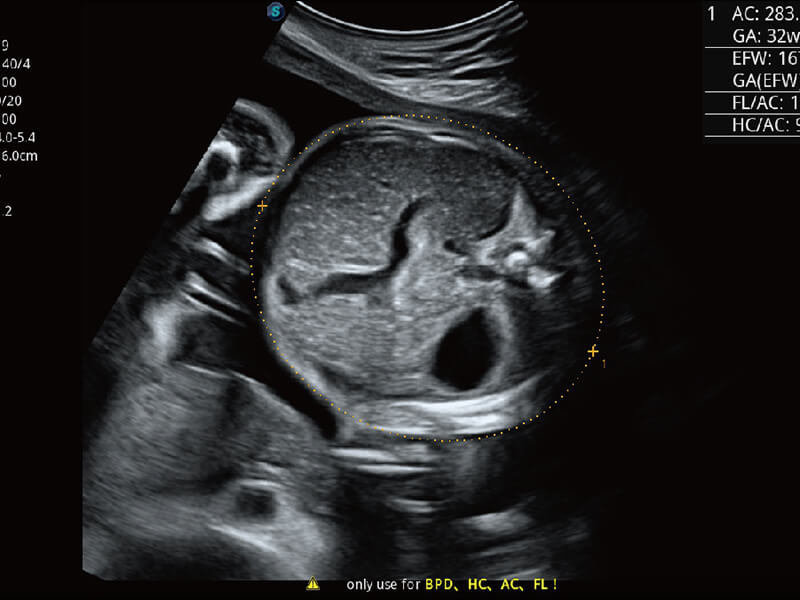

性能优异的硬件架构,极大提升超声系统的运行效率和数据处理能力。相比以往超声成像系统,Wis+平台为您带来极快的响应速度和成像帧频,提升检查流畅度。

超宽频带技术,为容积成像带来优质的二维图像基础,为您呈现丰富的结构细节,栩栩如生地展示宝宝的宫内形态以及各种组织的立体结构。